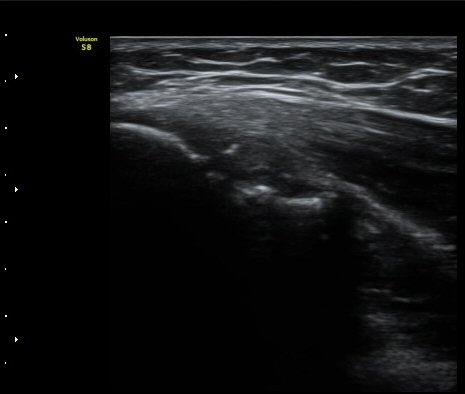

ÃÊÀ½ÆÄ °Ë»ç

³»»ó°ú Á¾´Ü¸é°Ë»ç»ó  ³»ÃøºÎÀδë Àú¿¡ÄÚ ºÎÁ¾°ú ³»»ó°ú ÀÎ´ë ºÎÂøºÎ ÇÇÁú°ñÀÇ ºÒ±ÔÄ¢º¯È­¿Í

°ñÆíÀÌ °üÂûµÇ°í(±×¸² 1, 2, 3, 4) ÀÌ·±¼Ò°ßÀº °ÇÃø°ú ºñ±³ÇÏ¸é ´õ¿í ¶Ñ·ÈÇÔ(±×¸² 5, 6).